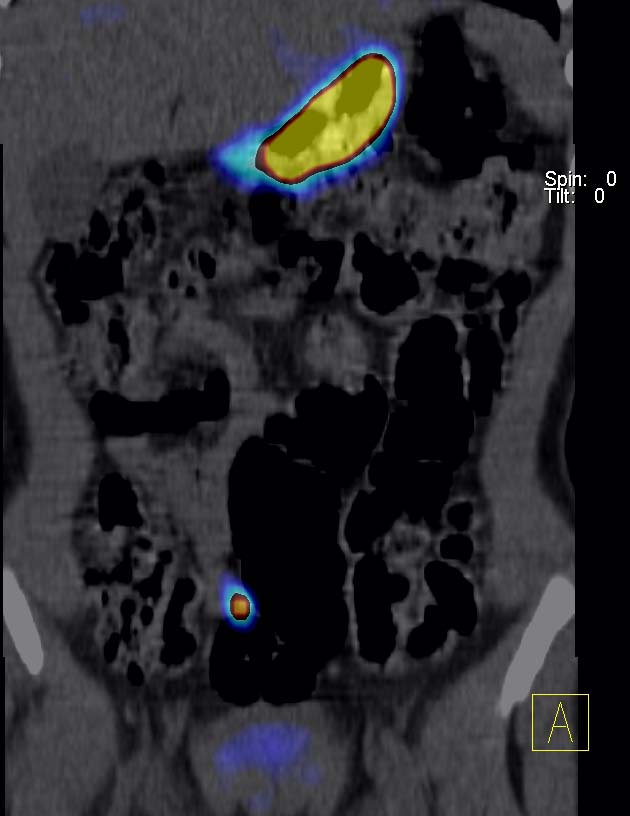

SPECT-CT : fixation focale sur une anse grêle.

La topographie et la cinétique de captation du foyer est très évocatrice d’une muqueuse gastrique ectopique (diverticule de Meckel).